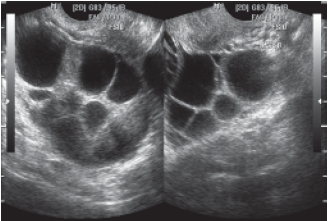

1. Ovarios

1. Luteoma del embarazo

1. Quistes de la teca luteínica